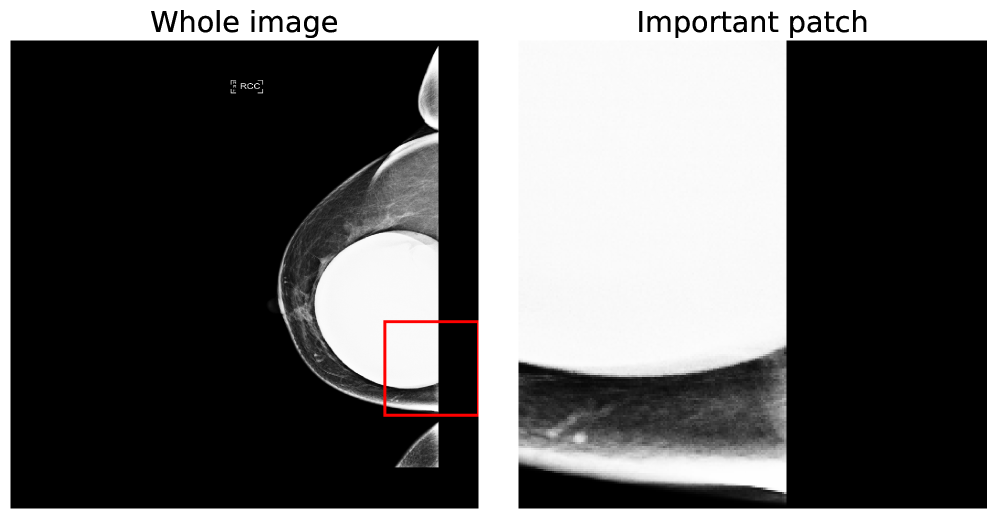

Similarly, we can perform the same inspection for random iamges of the RSNA-SMBC dataset in Figure 10. Note that this dataset is not as obvious to non-medical professionals but each instance is a true-positive identification.

VSA-MIL further succeeds in detecting more than just the singular region of malignancy. This is confirmed by visualizing all overlapping sub-regions that are detected as positive malignancy, demonstrated in Figure 11. We make note that in some cases adjusting the size of the patch may yield more intuitive results depending on the size of what needs to be detected, but did not alter this to be aligned with prior articles and the patch size previous used.